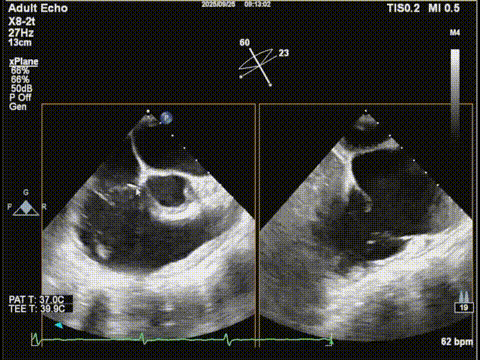

三尖瓣胃底界面

三尖瓣胃底界面color

随后,团队将操作重点转向三尖瓣。在胃底食道超声界面引导下,调整夹合器位置并成功跨瓣,在确保充分捕捉前叶与膈叶后释放夹合器。术后三尖瓣反流明显减轻,遂完全释放夹合器,手术顺利成功。

调整胃底界面评估三尖瓣夹子位置

夹合器钳夹三尖瓣瓣叶后评估